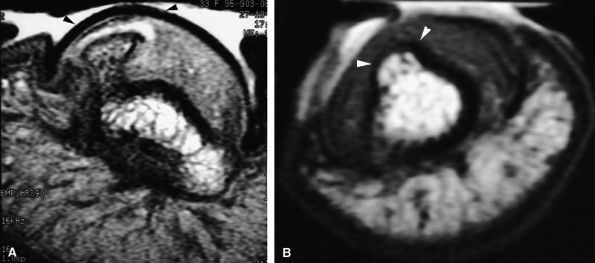

The vascular type is composed of numerous vascular lumens. Enhancement is very high after injection of gadolinium, and the signal is high on T2-weighted images.296 MR angiography shows early enhancement in the arterial phase that increases on the delayed venous acquisition (Fig. 11.128).297,298

-

The cellular or solid type of glomus tumor is composed mainly of a proliferation of epithelioid cells (glomus cells) with a relative paucity of vascular lumens. This type of tumor is difficult to detect with MR imaging. Its signal is close to that of the normal dermis of the nail bed on all sequences (Fig. 11.129). Injection of gadolinium, even with MR angiography, is of little use. Using 3D gradient-echo imaging with thin contiguous slices is the most helpful by depicting a peripheral capsule or a slight bone erosion on the dorsal aspect of the phalanx.

The mucoid type of glomus tumor is characterized by mucoid degeneration of the stroma, which demonstrates mild enhancement after gadolinium administration. On T2-weighted images it is seen with very high signal intensity because of the large amount of water in the stroma (Fig. 11.130). Recently it has been shown that this subtype of glomus tumor coexpresses alpha-smooth muscle actin and CD34 in neoplastic cells, an important finding regarding the differential diagnosis of these lesions and the relationship of perivascular neoplasms.299,300

FIGURE 11.128 ● Vascular-type glomus tumor (asterisk) of the nail bed with the most common signal characteristics. (A) Axial T2-weighted image. T1-weighted images before (B) and after (C) injection of gadolinium. (D) MR angiogram. The tumor is located on the midline with an underlying bone erosion (arrowheads). The signal is high on T2-weighted images and slightly high on T1-weighted images. There is strong post-contrast enhancement on T1-weighted images and MR angiography.

FIGURE 11.129 ● Solid-type glomus tumor. (A) Axial T2-weighted image. T1-weighted image before (B) and after (C) injection of gadolinium. The tumor is in the lateral part of the nail bed (arrows) and is faintly visible on all sequences.

FIGURE 11.130 ● Mucoid-type glomus tumor. (A) Axial STIR image of a glomus tumor demonstrates very high signal in the lateral nail bed (asterisk). (B) On an MR angiogram, faint tumor enhancement is seen on delayed sequences (arrows).